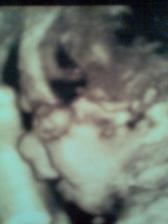

- 27.6.2009: začíná mě píchat v bříšku. když se ohnu nebo udělám jiný pohyb píchne mě v děloze. naštěstí je moje mamka zdravotní sestra a ta mě uklidnila, že se nemusím bát, protože se roztahuje děloha tak to bude trošičku nepříjemné. Ufff... -7.7.2009: Dnes jsme absolvovali druhou poradnu. Bohužel stále nevím pohlaví, ale to nevadí. Podle fotečky to stejně bude celý tatínek 🙂 Podle MS 16+5 a podle UZ 16+7. -4.8.2009: Hurááááá, je to chlapeček!!!! 19cm a 247gramů 🙂 - 18.8.2009: Byli jsme na sono srdíčka a vše je v pořádku a pan doktor potvrdil, že jde o klučíka 🙂 19.9.2009: Dneska mě ten malý mrňous poprvé kopnul.Seděla jsem na zahradě, hladila si bříško a vykládala si z našima a malý se asi chtěl zapojit do debaty. Předtím jsem cítila jen letmé pohyby,ale tohle mě málem rozplakalo, protože na to jsem se hrozně moc těšila 🙂 1.9.2009: Volal nám pan doktor, jestli bychom mu nemohli jít modelem na nový 3D ultrazvuk, samozřejmě jsme souhlasili. Bohužel jsme hodinku čekali v čekárně a Jiřík mi mezitím v bříšku usnul a to tak nešikovně že si ručičkama zakrýval obličej, takže i fotečka je trošku nepovedená 🙂 ale to nevadí, i tak to bylo krásné. Samozřejmě jsem přepočítala prstíky... příště s námi jde i tatínek 🙂